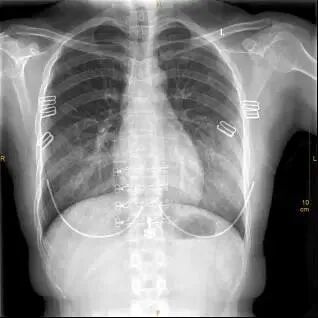

①这个文胸结构比较复杂……

X光拍片为什么要等【影像科普】拍片为什么会要求脱衣服?_https://www.jmylbn.com_新闻资讯_第4张